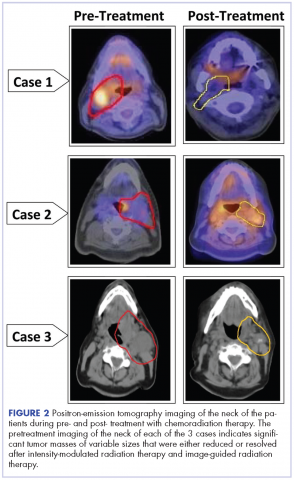

A CT scan of the chest was clear with no evidence of malignant involvement. A subsequent CT scan of the neck revealed a primary neoplasm of the right faucial tonsil measuring 3.3 x 3.0 cm and associated with right level II, level III, and level IV pathological lymphadenopathy. Positron-emission tomography (PET) imaging of the neck revealed a right tonsillar lesion of 2.7 x 3.0 cm involving the right parapharyngeal space (Figure 2, Case 1). The standardized uptake value (SUV) of the PET scan of the primary lesion was measured at 7.3. A cluster of right level II cervical nodes measuring 3.2 x 2.5 cm had an SUV of 3.5. A 1.0-cm right level III jugular node was also seen with an SUV of 1.6, and a right level IV lymph node measuring 1.5 x 1.0 cm was seen with an SUV of 1.8. No other lesions were noted. The tumor stage was T2N2bM0, a stage IVa disease.

The follow-up after 41 months indicated that the patient had no evidence of recurrent disease (Figure 2, Case 1). Posttreatment magnetic-resonance imaging (MRI) of the neck also indicated no evidence of residual tonsillar cancer. The patient’s demographics, tumor characteristics, and the treatment details are summarized in the Table.

The pathology of the right tonsil was found to be benign. Histology of the left tonsil revealed invasive squamous cell carcinoma. The resected tumor size measured 3.7 x 2.7 x 2.5 cm. The tumor was moderately differentiated involving the deep surgical margins. No lymphovascular invasion was seen. A PET scan revealed a mass arising from the left tonsillar pillar measuring 3.6 x 2.6 x 3.3 cm with deviation of the epiglottis posteriorly nearing the left vallecula. In addition, multiple large cervical nodal lesions in the left level II nodal chain were seen, with the largest measuring 3.1 x 3.0 x 4.5 cm with an SUV of 3.4. Displacement of the left submandibular gland with several further enlarged level II lymph nodes was observed. In the region of left vallecula, there was soft tissue thickening with increased activity measuring 2.7 x 1.5 cm, likely crossing the midline with an SUV of 5.5. The rest of the neck was negative for metastatic involvement (Figure 2, Case 2). The tumor stage was T3N2Mx, a stage IVa disease.

The patient had a Port-A-Cath placed, which caused a hemothorax after placement of the port and delayed initiating his treatment. A pretreatment MRI scan of the neck revealed multiple conglomerate hypodense peripherally enhancing nodular areas in the left neck posterior to the left submandibular gland deep to the parotid tail worrisome for necrotic lymphadenopathy. The patient underwent a course of hyperfractionated IMRT-IGRT in 67 fractions of 120 cGy twice daily for a total dose of 8,040 cGy to the primary tumor site.16 The patient had a port and PEG tube prior to initiating his radiation therapy. He received IMRT-IGRT with concurrent chemotherapy that was selected based on the recommendation of his genomic testing.17,18 The chemotherapy regimen used included carboplatin (300 mg weekly) and docetaxel (400 mg weekly). The patient had a treatment break because he was hospitalized for anemia and pancytopenia from his chemotherapy and he received supportive cancer care with epoetin alfa.A post therapy PET scan was negative for evidence of hypermetabolic malignancy; however, a 3.3 x 2.7 cm calcified lesion representing likely level III jugular lymph node exhibited no measurable activity at that time. The follow-up after 40 months indicated that the patient had no reported recurrence of the disease (Figure 2, Case 2). The patient’s demographics, tumor characteristics, and the treatment details are summarized in the Table.

A 53-year-old white man, who had no smoking or tobacco history but who was exposed to chemicals including sulfuric acid, hydrogen chloride gas, and glycols at work, presented initially with a sore throat that became more painful over time. His ENT specialist referred him for a CT scan of the neck, which revealed a left-sided neck mass measuring 2.5 cm in diameter posterior to the submandibular gland and lateral to carotid sheath and anterior to the triangle (Figure 2, Case 3). The mass appeared to be encapsulated. There was a lobulated spherical mass in the left supraglottic area with formation of the airway of the pyriform sinus and additional anterior vascular involvement was noted. The mass measured 3.6 cm in transverse diameter.

After completion of his radiation therapy, chemotherapy was changed based on genomic testing from single agent to doublet with carboplatin (area under the curve (AUC) dose of 2 or 200 mg, weekly) plus docetaxel (25 mg/m2 weekly for 3 weeks and 1 week off ).17,18 A PET scan after chemoradiation therapy revealed a marked anatomical improvement in the primary neoplastic disease seen in the faucial tonsil. The tonsillar mass noted previously had almost completely resolved over the interval, with only a mild persistent asymmetrical thickening of around 1.5 cm, with a peak SUV of 2.0. A lymph node of 2.8 x 2.0 cm was present anterior to the left sternocleidomastoid muscle exhibiting SUV of only 1.8. No other abnormal lesions were noted (Figure 2, Case 3). The patient continues to do extremely well without local recurrence of the disease 46 months after radiation therapy (see Table for patient demographics, tumor characteristics, and therapy details.)